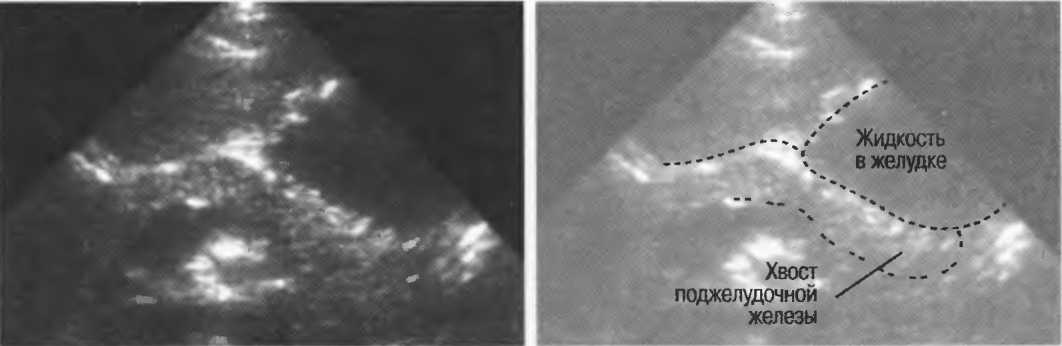

Акустическое усиление и акустическая тень

Чистые жидкости проводят ультразвуковой сигнал без существенного ослабления, поэтому отраженные эхосигналы, идущие от тканей, расположенных за жидкостью, обычно усилены (более яркие). Этот феномен известен как «акустическое усиление» (рис. 10а). Прием достаточного количества жидкости для заполнения желудка дает смещение кишечника, содержащего газ, и тем самым создает акустическое окно. Это особенно полезно для визуализации тела и хвоста поджелудочной железы.